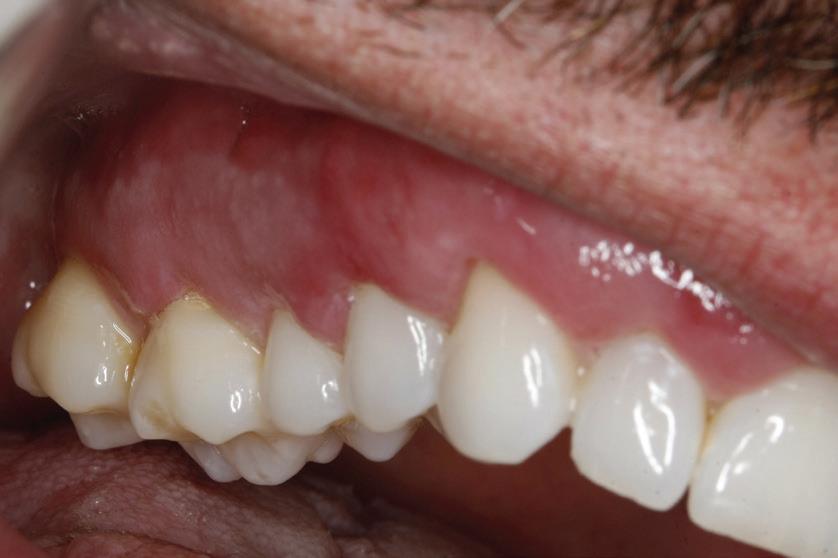

Un pacient caucazian în vârstă de 77 ani s-a prezentat la clinica autorului după cinci ani în care nu a fost la niciun control stomatologic. Examinarea clinică a arătat o pierdere semnificativă de os, parodontită cronică și multiple edentații care au destabilizat ocluzia. Pacientul a raportat sensibilitate la rece la nivelul primului molar drept inferior nr. 46, în special la ingerarea de lichide reci. Radiografia periapicală a confirmat constatările examenului clinic; în

plus, s-a detectat și prezența unei carii radiculare la nivelul rădăcinii distale a aceluiași molar, cu răspuns pozitiv la testul de sensibilitate (fig. 1-2).

1. Situația clinică inițială.